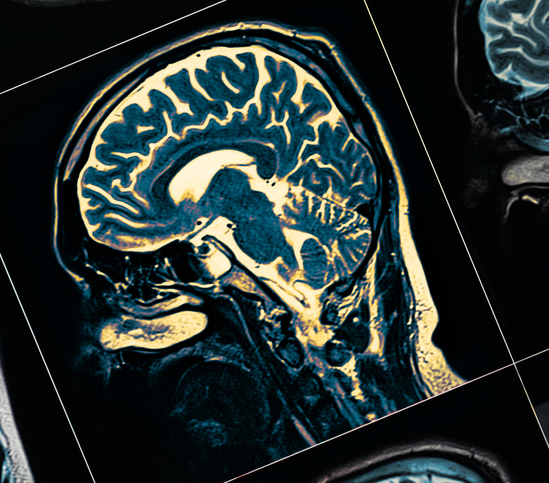

Negli ultimi anni sono stati avviati numerosi progetti di ricerca che sperimentano l’uso delle cellule staminali nei pazienti con Parkinson, tra cui gli studi giapponese e americano pubblicati su Nature, e il progetto europeo STEM-PD. Ma perché proprio il Parkinson, rispetto ad altre malattie neurodegenerative? «Il Parkinson è una malattia che, a differenza dell’Alzheimer, potrebbe rispondere più facilmente a un intervento cellulare mirato», spiega il professor Fabio Blandini, Direttore Scientifico dell’IRCCS Policlinico Maggiore di Milano. «È caratterizzato da una lesione relativamente circoscritta, localizzata principalmente nella substantia nigra, una regione del mesencefalo». I neuroni di quest’area producono dopamina, un neurotrasmettitore essenziale per la regolazione dei movimenti. La loro degenerazione è la principale causa dei sintomi motori tipici del Parkinson. «Intervenire localmente potrebbe quindi essere efficace». Attualmente, l’unico trattamento disponibile per alleviare i sintomi motori è la levodopa, utilizzata ormai da circa sessant’anni: un precursore della dopamina che viene convertito in dopamina nei neuroni ancora funzionanti. «Si tratta però di una terapia sintomatica, che non blocca la progressione della malattia», sottolinea Blandini.

L’obiettivo delle nuove terapie sperimentali è quello di sostituire i neuroni dopaminergici persi con nuovi neuroni generati in laboratorio. I due studi pubblicati su Nature sono simili: a un gruppo di pazienti (una decina, con un’età media di 60 anni) sono state iniettate cellule staminali differenziate in precursori di neuroni dopaminergici, in una zona specifica del cervello (il corpo striato). A distanza di un anno e mezzo o due, non sono emerse reazioni avverse gravi, e sono stati osservati i primi segnali – ancora molto preliminari – di efficacia: un miglioramento delle funzioni motorie. «Tuttavia, questi studi non erano disegnati per misurare l’efficacia clinica, ma per valutare la sicurezza e la tollerabilità del trattamento», precisa Blandini. «Uno dei rischi maggiori legati all’uso delle cellule staminali è la possibilità che proliferino in modo incontrollato, dando origine a tumori. Questo, fortunatamente, non si è verificato». Le cellule iniettate sono rimaste localizzate nell’area bersaglio e hanno iniziato a produrre dopamina. Negli Stati Uniti è attualmente in corso uno studio di fase 3 che coinvolgerà 102 pazienti. Questo studio clinico randomizzato valuterà l’efficacia della terapia, confrontando i risultati tra chi riceve le cellule staminali e chi no.